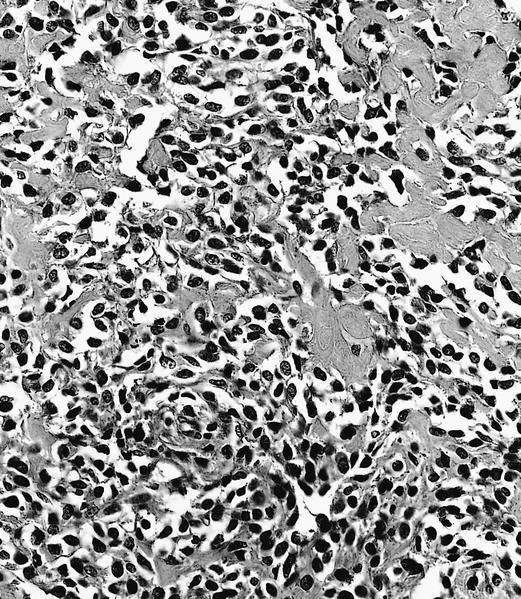

- Conventional (high grade intramedullary) osteosarcoma (Eur J Cancer 2002;38:1218, Am J Clin Pathol 2006;125:555):

- Permeative growth: intramedullary permeative growth (replacement of medullary space, surrounds and erodes native trabeculae, fills Haversian systems) and cortical destruction with soft tissue invasion

- Neoplastic cells: marked atypia (pleomorphic, hyperchromatic)

- Multiple cell morphologies often present in 1 tumor (epithelioid, plasmacytoid, spindled, small round cells, clear cells, giant tumor cells)

- Mitotic figures are easily demonstrable and atypical mitotic figures may also be identified

- Neoplastic bone (necessary for diagnosis): no minimum quantity necessary

- Most common: filigree / lace-like disorganized woven bone (intimately associated with neoplastic cells)

Microscopic (histologic) images

Contributed by Jesse Hart, D.O., Borislav A. Alexiev, M.D. and AFIP

Practice question #2

A 16 year old boy had a biopsy from a 16 cm mass in the proximal humerus (see image). Which of the following is true?

C. Treatment will include neoadjuvant chemotherapy followed by resection. This is a conventional high grade osteosarcoma.